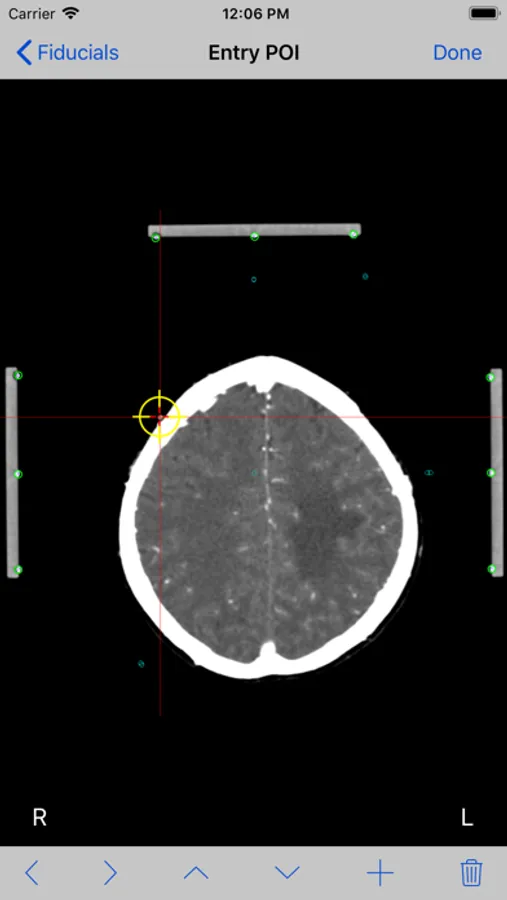

Mark each fiducial on the image and tap the Done button. Mark the entry point and tap the Done button.

9. If Two Image method was selected, the entry point image will be shown. Tap the Done button.